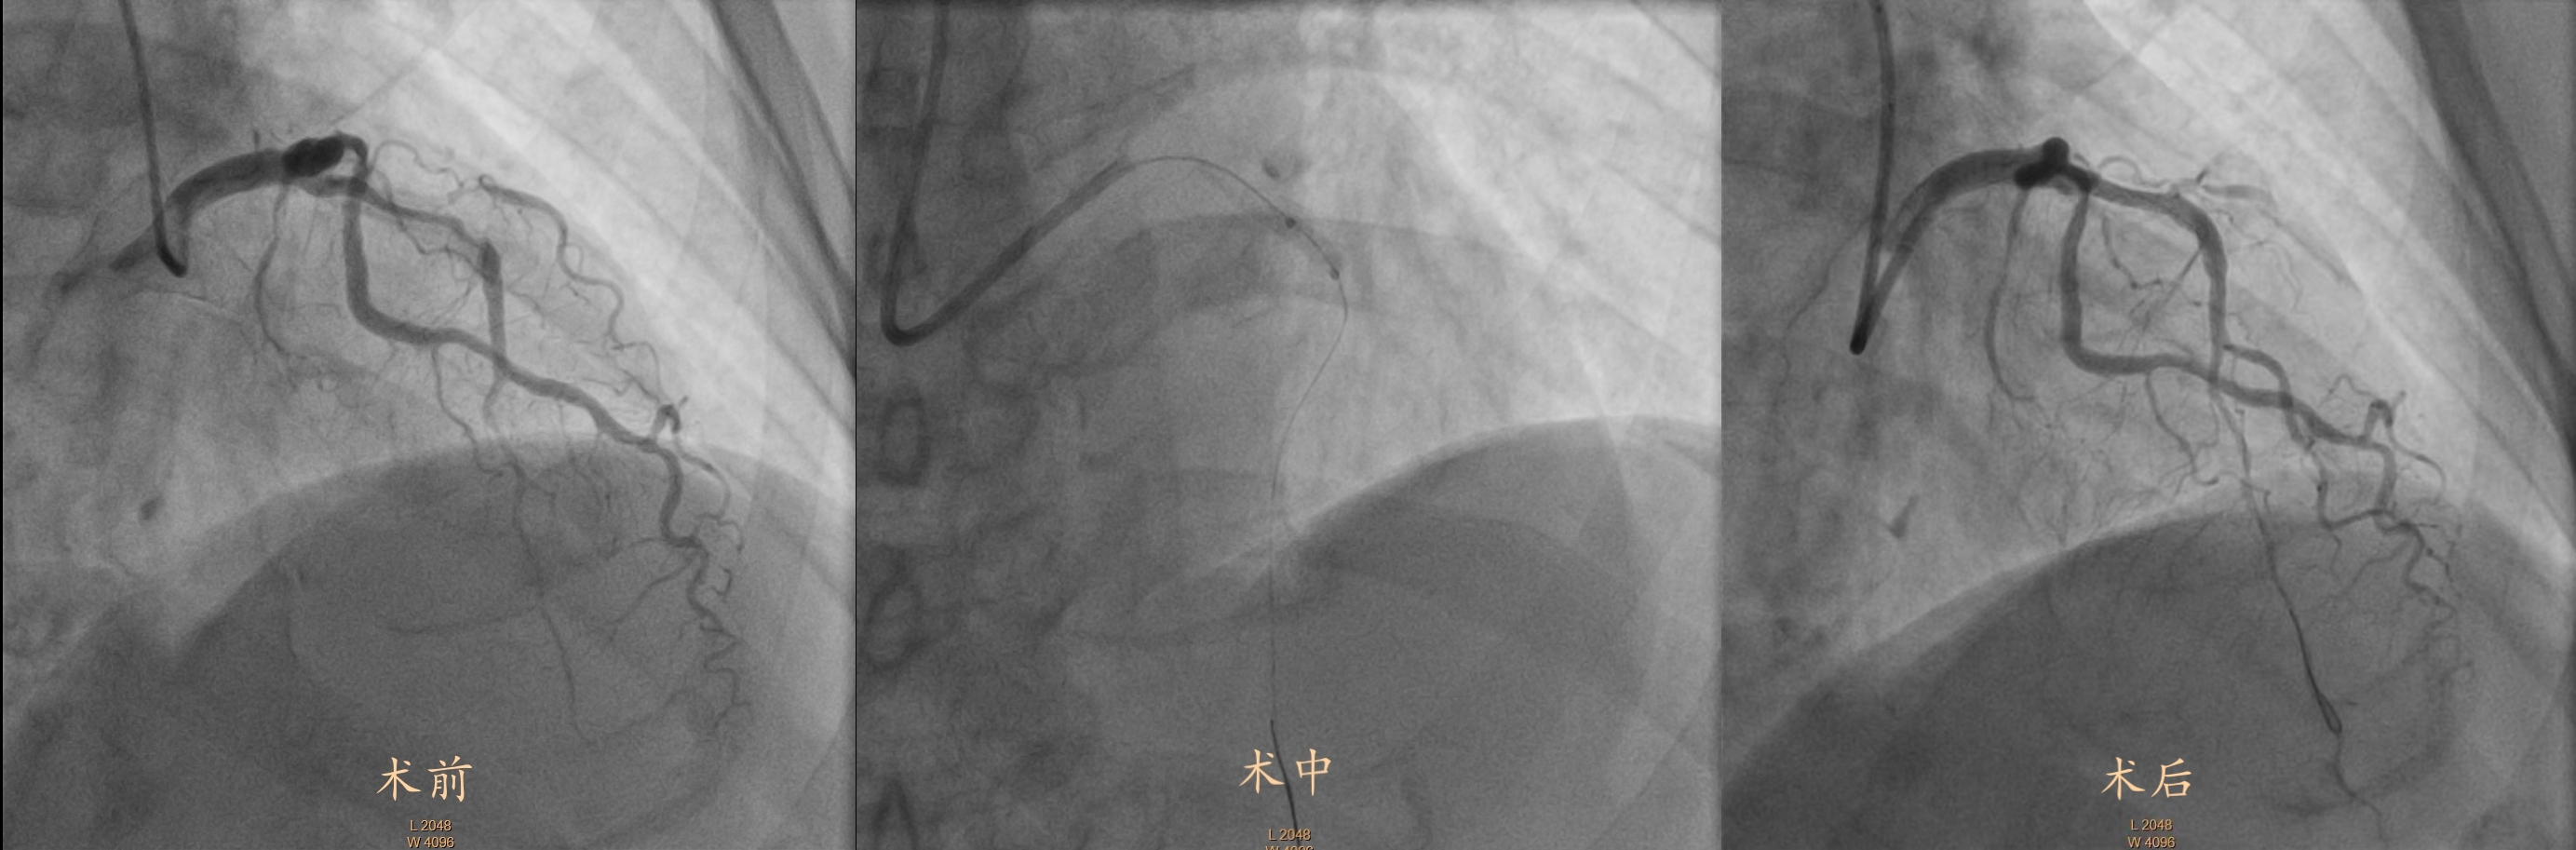

近日,由周口市中醫(yī)院心病一病區(qū)主任李斌、副主任醫(yī)師湯繼海帶領(lǐng)的介入診療團(tuán)隊(duì)成功完成了院內(nèi)首例應(yīng)用沖擊波球囊技術(shù)治療重度冠脈鈣化病變患者的手術(shù),標(biāo)志著我院心血管介入治療邁入了一個(gè)新的時(shí)代。隨著技術(shù)的不斷優(yōu)化和臨床經(jīng)驗(yàn)的積累,沖擊波球囊有望在更多復(fù)雜病變中發(fā)揮重要作用,為冠心病患者提供更優(yōu)質(zhì)的治療選擇。

患者75歲王老先生,1月前因心絞痛發(fā)作于當(dāng)?shù)蒯t(yī)院診斷冠心病,因長期有“高血壓”、“2型糖尿病”,于當(dāng)?shù)蒯t(yī)院行冠狀動脈造影提示冠狀動脈左前降支近端彌漫狹窄伴重度鈣化,因鈣化較重,當(dāng)?shù)蒯t(yī)院建議患者外科搭橋,因患者恐懼“外科手術(shù)”,故選擇藥物保守治療,但心絞痛反復(fù)發(fā)作,日常活動受限。患者及其家屬飽受折磨,后前來我院心病科住院治療,李斌主任團(tuán)隊(duì)多次開展術(shù)前討論,結(jié)合患者家屬意愿,最終決定行前降支血管病變處沖擊波球囊應(yīng)用,王先生術(shù)后恢復(fù)良好!他激動地表示:“手術(shù)過程很快,幾乎沒有不適感,胸痛也完全消失了。感謝醫(yī)生和這項(xiàng)新技術(shù),讓我重獲健康!”

冠脈鈣化是一種由鈣質(zhì)沉積在血管壁引發(fā)的病變,令血管變得堅(jiān)硬,極大增加了介入治療的難度和風(fēng)險(xiǎn)。而采用沖擊波球囊技術(shù)(血管內(nèi)沖擊波鈣化碎裂術(shù)),對患者嚴(yán)重鈣化的血管進(jìn)行介入治療時(shí),將沖擊波球囊準(zhǔn)確送到病變部位,發(fā)射沖擊波能量使鈣化病變斷裂松解,隨后順利植入支架,整個(gè)手術(shù)用時(shí)約一小時(shí),術(shù)后患者癥狀明顯改善。